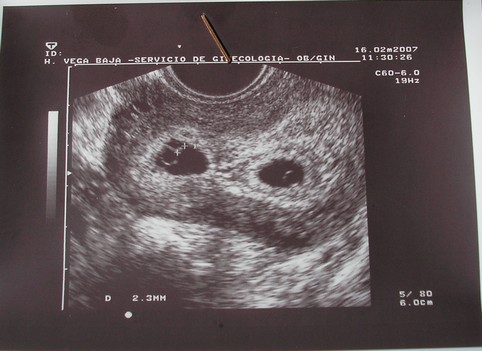

Ugye mi ahhoz tartozunk, de ha a kis manók nem ketten jöttek volna, nálunk a tervezett kettőn kivűl több nem lenne.

Aztán mikor kiderült, hogy kettő, akkor már tudtam, hogy az életről szőt terveimet módosítani kell.